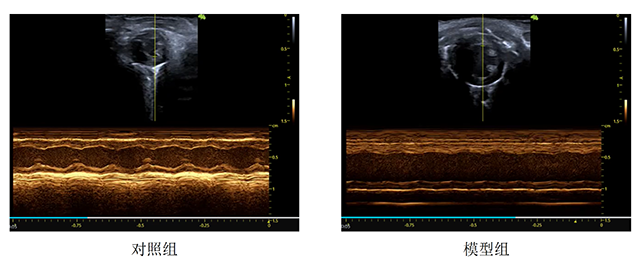

评价指标:EF、FS及超声心动图

超声心动图